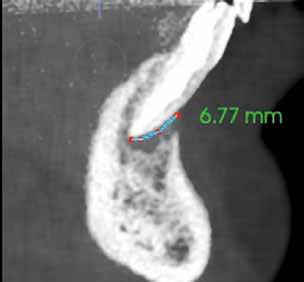

1. ábra: A 15-ös foggyökér meziális felszíne mellett látható radiolucens elváltozás, illetve a felvételen látható a korábban behelyezett gyökértömés, a parapulpális csap segítségével elhorgonyzott csonkfelépítés és a fogat borító cirkonkorona. –2. ábra: A saggitalis irányú CBCT-metszeten jól megfigyelhető az állcsontgerincet elérő radiolucens elváltozás. – 3. ábra: Az axiális irányú CBCT-metszeten egyértelműen látható a kezeletlen palatinális gyökércsatorna, valamint a radiolucens elváltozás mezio-disztális kiterjedése is jól megítélhető. – 4. ábra: A palatinális gyökércsatorna szelektív endodonciai kezelése során először gyógyszeres zárás került behelyezésre. – 5. ábra: A gyógyszeres zárás során alkalmazott kalcium-hidroxid alapú paszta a szulkuszon keresztül a szájüregbe extrudálódott. – 6. ábra: A gyökértömő anyag a középső és apikális gyökéri harmad határán lévő laterális csatornán keresztül a periapikális térbe extrudálódott. 7. ábra: A kezelések befejezését követően 4 évvel készült röntgenfelvételen jól látható a csontállomány gyógyulása és a fiziológiás gyökérhártyarés újbóli kialakulása. –8. ábra: A peroperatív CBCT-felvétel alapján készített koronális irányú metszeten jól látható a gyökércsúcs körül lévő periapikális felritkulás. – 9. ábra: A kezelések befejezése után 4 évvel készített CBCT-felvételen a gyulladásos lézió teljes megszűnése észlelhető.

A CBCT-készülékek endodonciai alkalmazásának talán az az egyik legnagyobb előnye, hogy így olyan anatómiai struktúrák is láthatóvá válnak, amelyeket egyébként nem tudnánk detektálni panoráma, cephalo, vagy periapicalis felvételek segítségével. Mivel a CBCT-felvételek kiértékelése számítógép segítségével történik, így a felvételek vizsgálata során lehetőségünk van az adott területet több nézőpontból és több síkban is megvizsgálni. 2015 októberében egy korábban a rendelőnkben kezelt 55 éves férfi páciens azzal a céllal kereste fel ismét a rendelőnket, hogy másodvéleményt kérjen egy jobb felső kvadránsban található fogával kapcsolatban. Egy másik rendelőben történő vizsgálat során a panaszos fog törését vélelmezték és a fog eltávolítását javasolták, illetve arról is beszámolt, hogy az elmúlt hét során ezen a területen egy puha duzzanat is kialakult. A klinikai vizsgálat során a jobb felső első és második kisőrlő között (14–15) egy fluktuáló duzzanatot észleltünk az áthajlásban. Az 15-ös fog mesialis oldalán 12 mm mély tasakot szondáztunk. A páciens által hozott periapicalis felvételen a 15-ös fog gyökércsúcsának mesialis részén egy nagy kiterjedésű radiolucens elváltozás volt észlelhető (1. ábra). A saggitális síkban vizsgált CBCT-felvételen (Carestream CS 9000, Carestream Dental) a lézió valódi kiterjedése is láthatóvá vált (2. ábra). A megelőző endodonciai kezelések során csupán a bukkális csatorna került detektálásra és gyökértöméssel való ellátásra. Az axiális irányú CBCT-szeleteken egyértelműen látható volt az ellátatlan palatinális gyökércsatorna (3. ábra)

Először kalcium-hidroxid alapú ideglenes gyógyszeres zárás került a palatinális csatornába (UltraCal XS, Ultradent Products; 4–5. ábra), amelyet 6 hét után a végleges gyökértömés elkészítése előtt eltávolítottunk. A gyökértömés elkészítése során meleg vertikális kondenzációs technikát alkalmaztunk. Radiológiai felvételen megfigyelhető volt, hogy a gyökértömő anyag egy laterális csatornán keresztül kis mennyiségben a periapicalis térbe extrudálódott (6. ábra). A 4 évvel később készített kontrollfelvételeken a lézió gyógyulása volt megfigyelhető (7–9. ábra). A vizsgálati eredmények és a kezelés kimenetele egyértelműen igazolta, hogy nem gyökérfraktúrával álltunk szemben, tehát a kezdeti diagnózis tévesnek bizonyult. Ez is azt erősíti, hogy korlátozott mennyiségben rendelkezésre álló adatok alapján nem lehet pontos diagnózist felállítani. Manapság szinte elengedhetetlen a CBCT-felvételek endodonciai beavatkozások során történő használata, feltéve, ha ezek elkészítése során az ALARA elv (as low as reasonably achievable) betartásra kerül.